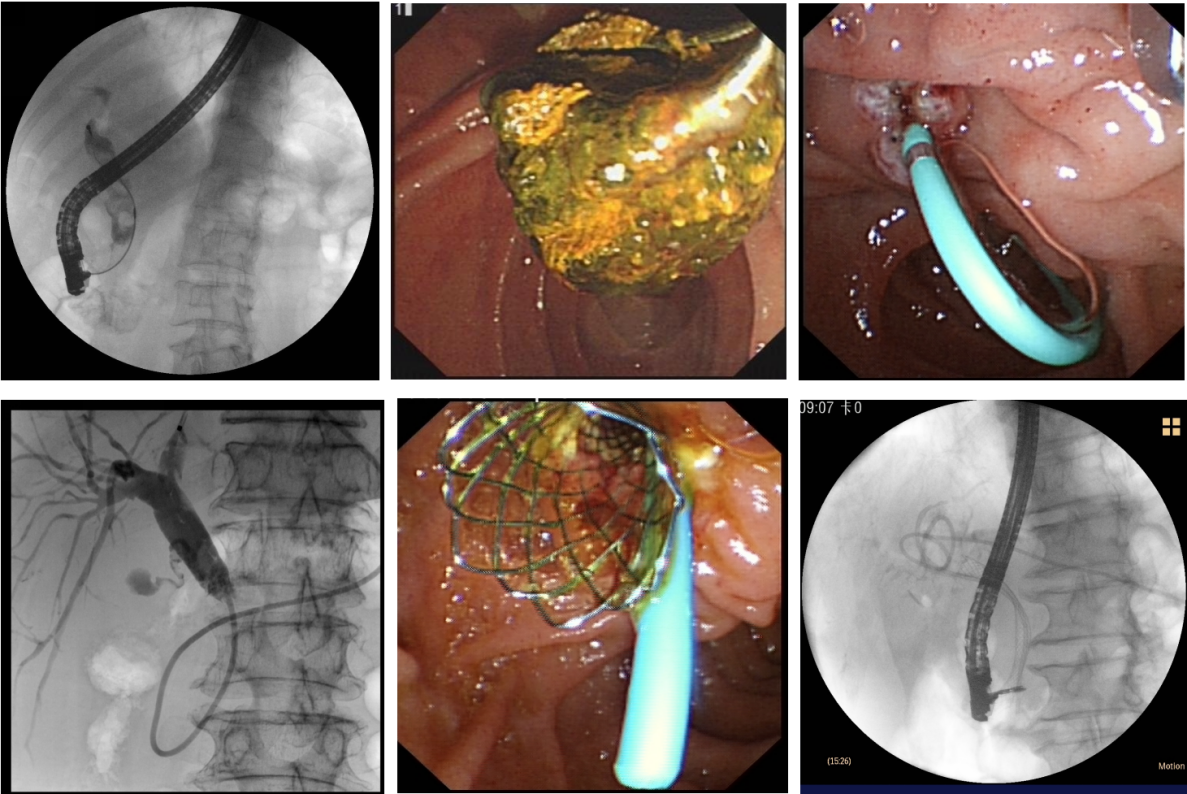

5. 胰管结石、梗阻的ERCP取石及引流。

ERCP

Spyglass